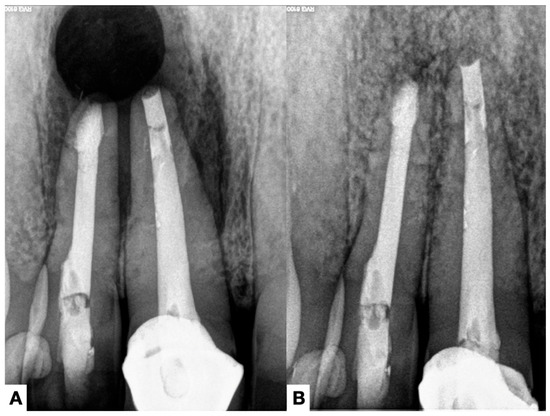

4.3. Radiographic Assessment

4.4. Treatment of the Extraradicular Infection